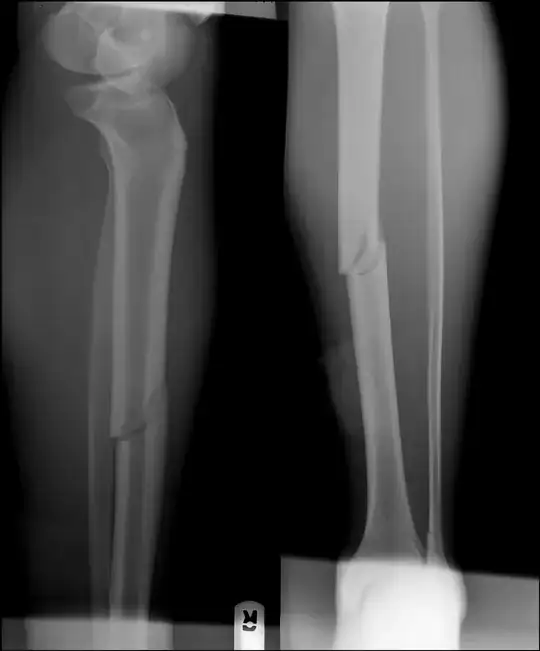

"Breaking" the fibula (or fibular ostotomy) in cases of tibial non-union is not unheard of, but I have absolutely no idea of how often it's done, or if the additional weight-bearing associated with it speeds tibial healing. But please note that you already have an angulated distal fibular fracture (look at the bone - the fibula - behind the tibia just above its concave surface in the leg on the left.) It looks to be at about 20°.

Oblique osteotomy for the correction of tibial malunion.

Danger Zones Associated with Fibular Osteotomy.